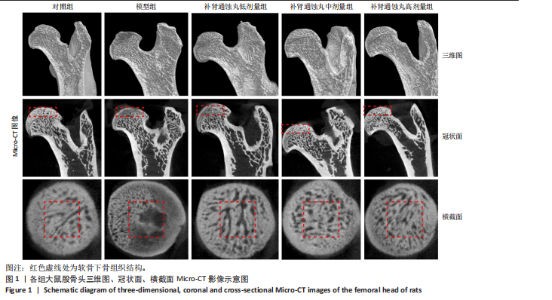

.1 实验动物数量分析 参加实验SD大鼠数量为50只,均进入结果分析。 2.2 Micro-CT检测结果 通过Micro-CT观察各组大鼠股骨头区域骨质变化,见图1。乙醇会导致大鼠股骨头软骨下骨骨量明显减少,骨小梁排列出现紊乱、稀疏等状况,而补肾通蚀丸能够改善上述情况,且呈现一定的剂量效应。模型组骨小梁厚度、骨小梁数目、骨体积分数、骨密度较对照组显著降低(P < 0.01),模型组骨小梁间隙较对照组则显著升高(P < 0.01)。经过不同剂量补肾通蚀丸干预后,各项指标均出现不同程度的逆向改变;其中,与模型组比较,补肾通蚀丸高剂量组骨小梁厚度、骨小梁数目、骨体积分数、骨密度均显著升高(P < 0.05),骨小梁间隙则显著降低(P < 0.05);与模型组比较,补肾通蚀丸中剂量组骨体积分数、骨密度显著升高(P < 0.05),骨小梁间隙则显著降低(P < 0.05);而补肾通蚀丸低剂量组仅在骨小梁间隙指标上较模型组显著降低(P < 0.05),见图2。 2.3 苏木精-伊红染色结果 与对照组比较,模型组大鼠股骨头出现核固缩现象,多见脂肪空泡,部分骨小梁出现断裂、变细;补肾通蚀丸低、中、高剂量组骨细胞核固缩和脂肪空泡较模型组有所减少;在整体结构方面,补肾通蚀丸低剂量组骨小梁变细现象较模型组未见明显改善,但断裂情况有所改善;而补肾通蚀丸中、高剂量组骨小梁断裂、变细情况较模型组均明显改善,见图3;在空骨陷窝率方面,模型组较对照组显著增高(P < 0.01);补肾通蚀丸中、高剂量组较模型组有所降低(P < 0.05),见图3。 2.4 免疫组化染色结果 与对照组比较,模型组NLRP3、Caspase-1、消皮素D蛋白表达明显增强,而Runt相关转录因子2、骨钙素、Ⅰ型胶原蛋白表达显著降低(P < 0.01);与模型组比较,补肾通蚀丸中、高剂量组能够显著降低NLRP3、Caspase-1、消皮素D蛋白表达,且促进Runt相关转录因子2、骨钙素、Ⅰ型胶原蛋白表达(P < 0.05),而补肾通蚀丸低剂量组骨钙素、Ⅰ型胶原蛋白表达有所上调(P < 0.05),其余指标则无明显差异(P > 0.05),见图4,5。 2.5 ELISA检测结果 与对照组比较,模型组大鼠血清中白细胞介素18和白细胞介素1β水平显著增高(P < 0.01);与模型组比较,补肾通蚀丸各剂量组大鼠血清中白细胞介素18和白细胞介素1β水平均显著降低(P < 0.01),且以一定剂量依赖方式递减,见图6。 2.6 Western blot检测结果 与对照组比较,模型组大鼠股骨头组织中NLRP3、cleaved-Caspase-1、Caspase-1、消皮素D、消皮"